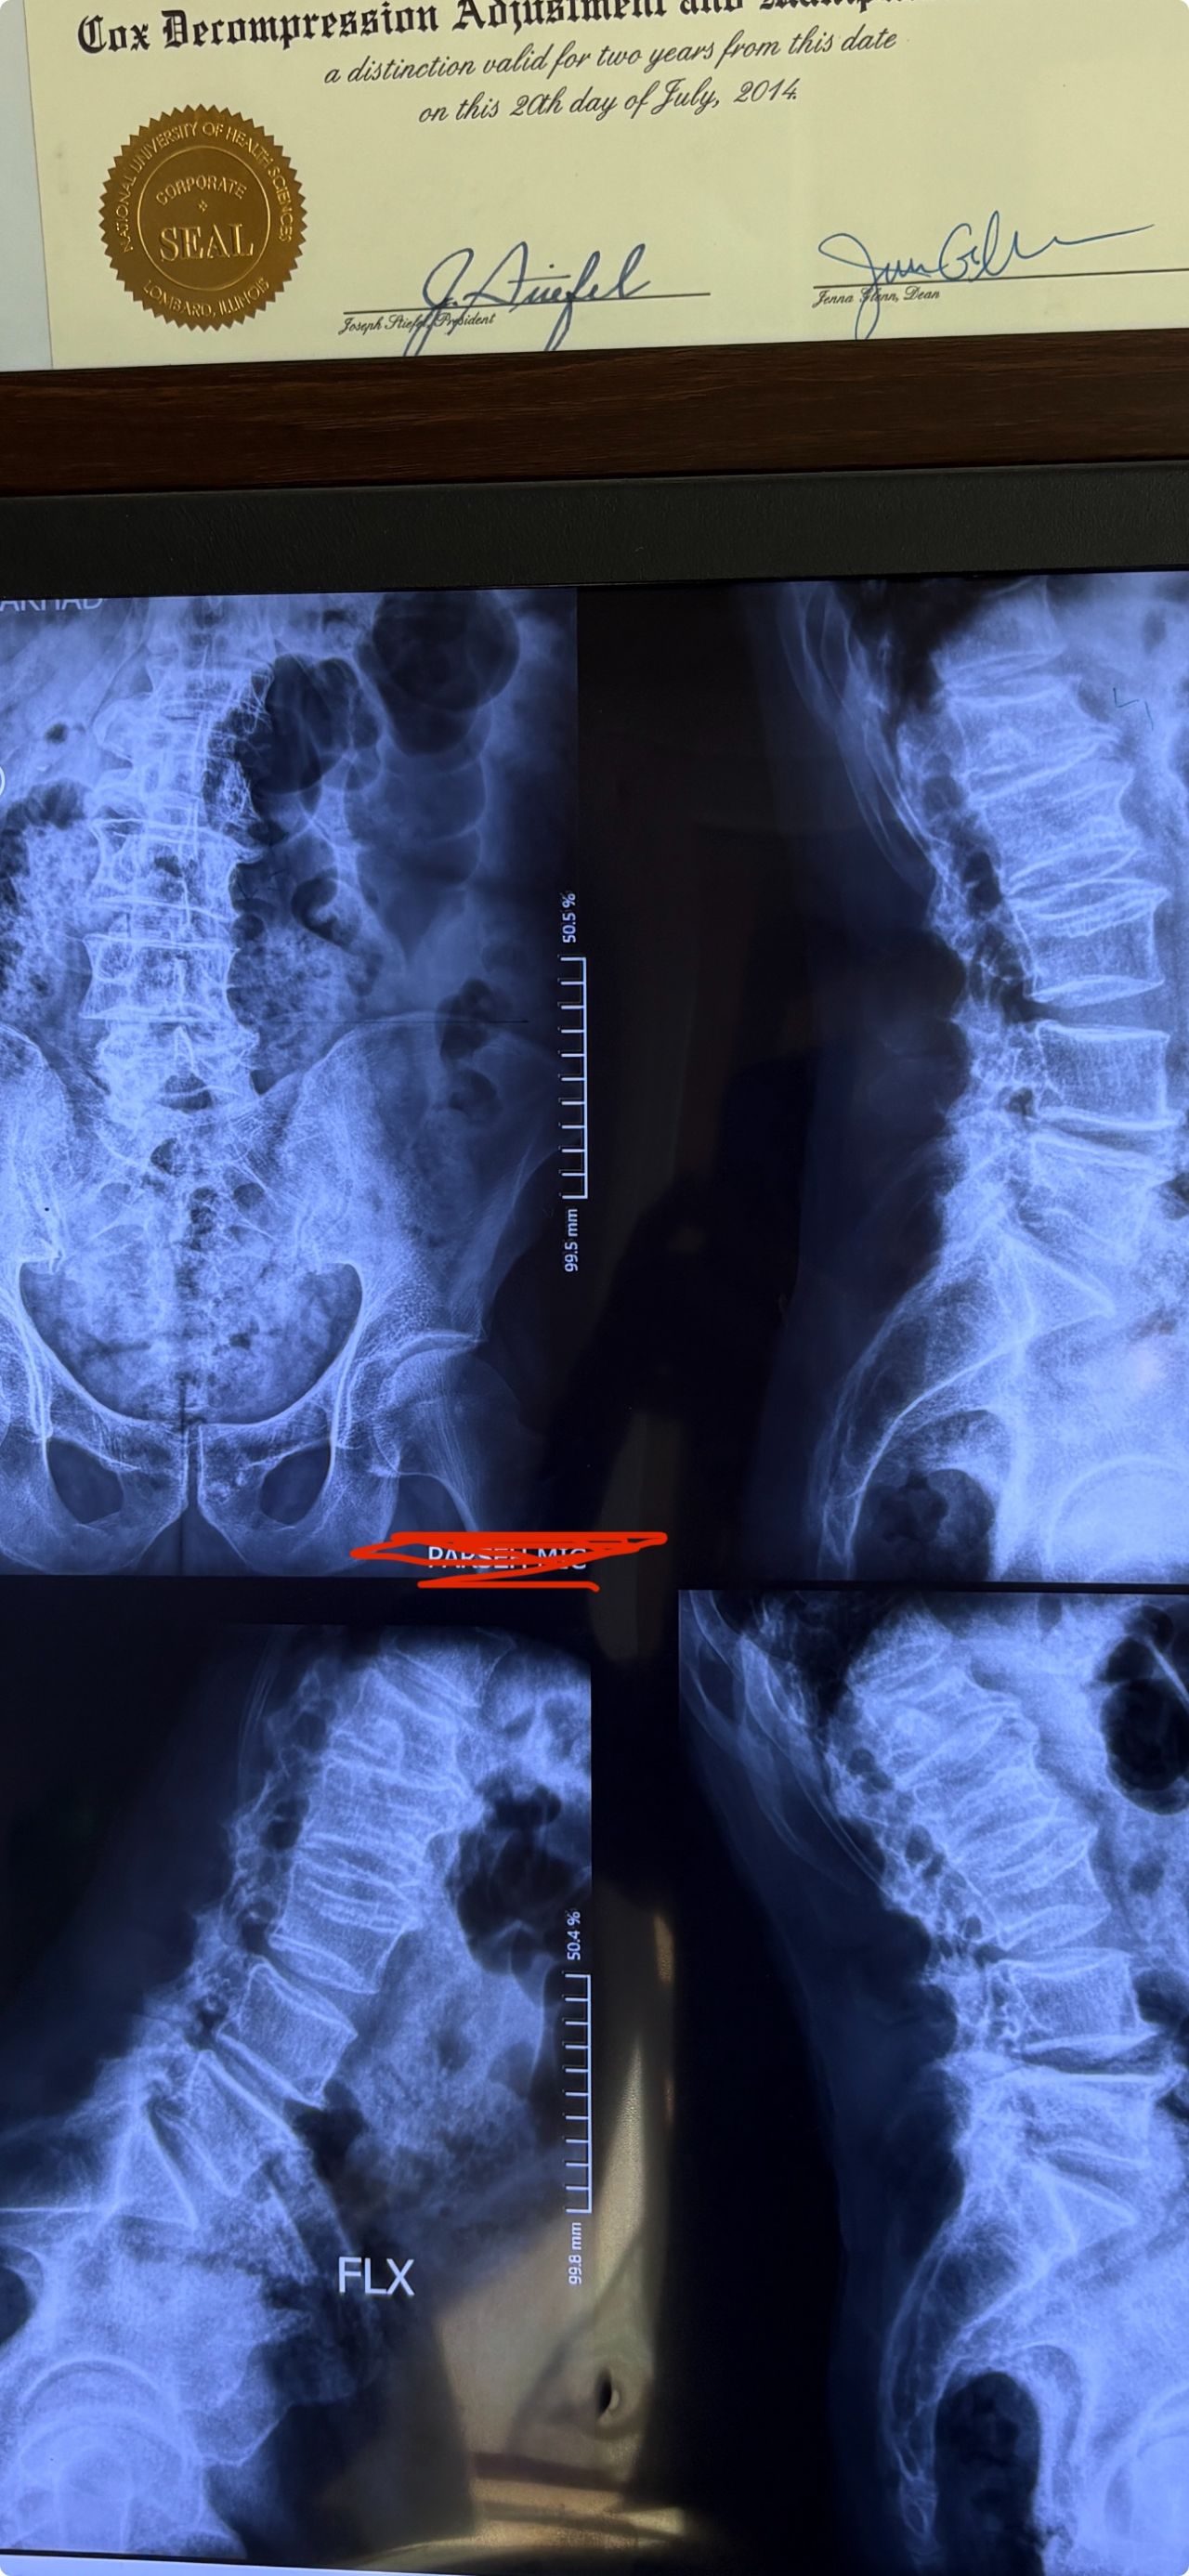

Cox decompression flexion axial distraction treatment on cox chiropractic spinal table

Chiropractic doctor should take cox technic courses for a few weeks and pass written and practical exame to get certified in this technic and have to buy the table from USA( US made)

For treatment of spinal disc herniations and stenosis